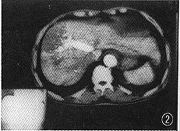

图2 CT增强可见肝中静脉提前显影,低密度区周边部开始强化